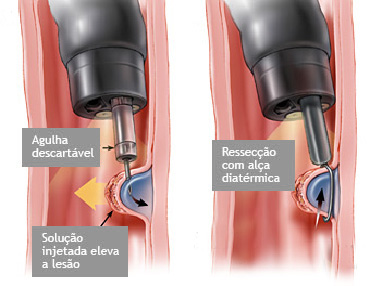

Mucosectomia é o procedimento realizado quando há necessidade de retirada de lesões maiores do trato gastrointestinal.

O exame de Mucosectomia é realizado através de injeção de liquido embaixo da lesão, através de uma agulha específica. Com isso a lesão se destaca das camadas mais profundas do intestino, diminuindo o risco de perfuração.

A retirada da lesão é feita com uma alça de polipectomia e o material é encaminhado para estudo anatomopatológico (no microscópio) da mesma forma que ocorre nas biópsias.

Mucosectomia

Para diminuir este risco, injeta-se com um uma agulha uma solução abaixo do pólipo para que ele levante e fique mais longe da parede do órgão. Após isto passa-se a alça diatérmica e realiza-se o

procedimento de polipectomia.

Tatuagem endoscópica

Nos casos onde existe a necessidade de revisão posterior do local onde foi feito o procedimento, seja por endoscopia ou por cirurgia, pode-se realizar a injeção de tinta na parede do órgão ficando assim esta região marcada permanentemente. Este procedimento é indolor e não leva a nenhum tipo de lesão do órgão marcado.